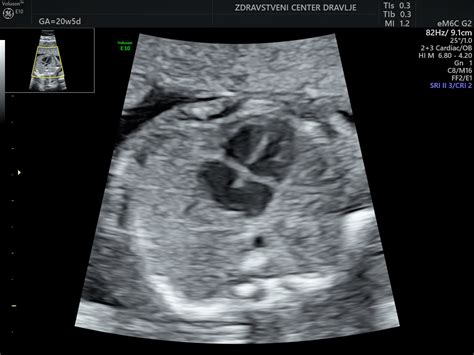

Pregled nuhalne svetline se običajno izvaja preko trebušne stene nosečnice (transabdominalni ultrazvok), le redko je potreben vaginalni ultrazvok (transvaginalni). Pred posegom je nosečnico praviloma prosijo, da izprazni mehur, kar omogoči boljšo vidljivost. Med pregledom ultrazvočna sonda omogoča opazovanje ploda v gibanju, ocenjuje se njegova velikost od vrha glavice do trtice, premer glavice, frekvenca srčnega utripa ter prisotnost in oblika nosne kosti. Nosna kost je namreč pomemben marker, saj je pri otrocih z Downovim sindromom pogosto odsotna ali prekratka.

Poleg meritve nuhalne svetline se med tem pregledom izvede tudi natančen ultrazvočni pregled zgodnje morfologije ploda. Ta vključuje oceno razvoja srca, glavice, možganskih struktur, želodčka, sečnega mehurja, okončin, hrbtenice ter preverjanje celovitosti trebušne stene in razvoja popkovnice. V določenih primerih je mogoče z manjšo stopnjo gotovosti napovedati tudi spol otroka.

V primeru povečane nuhalne svetline, a normalnih rezultatov genetskih testov, je lahko povečano tudi tveganje za srčne napake pri plodu. V takšnih primerih je priporočljiv natančen ultrazvočni pregled srca ploda, običajno med 14. in 16. tednom ter ponovno okoli 22. tedna nosečnosti.

- Morfologija ploda: Podroben ultrazvočni pregled anatomije ploda, običajno med 20. in 24. tednom nosečnosti.